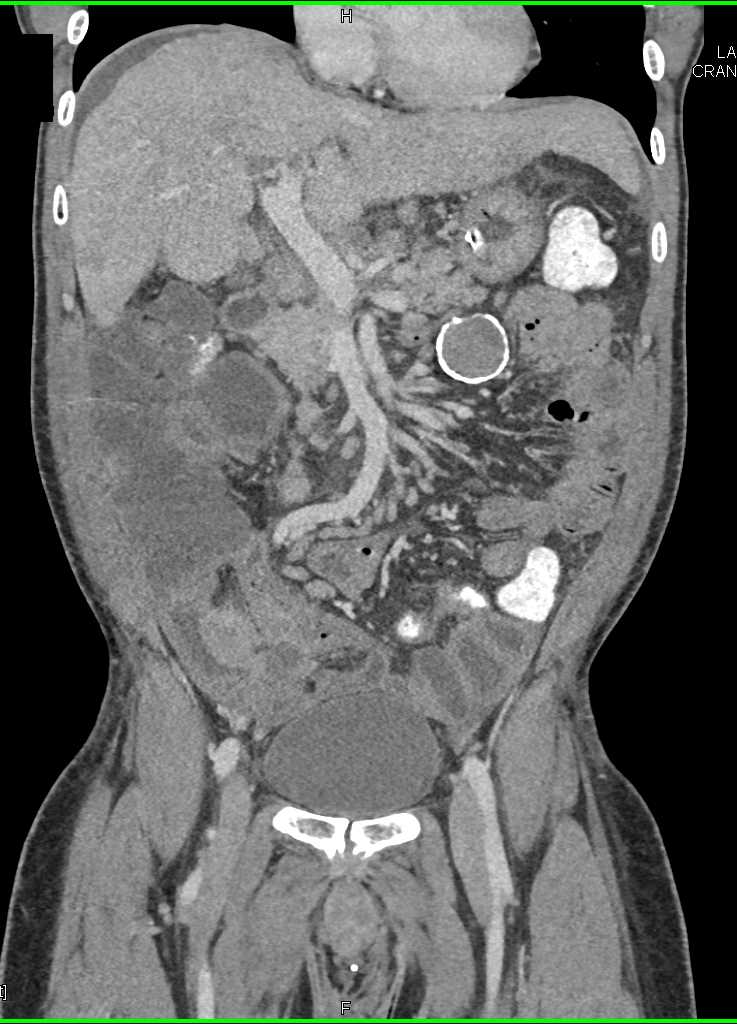

Small Bowel Carcinoma with Carcinomatosis